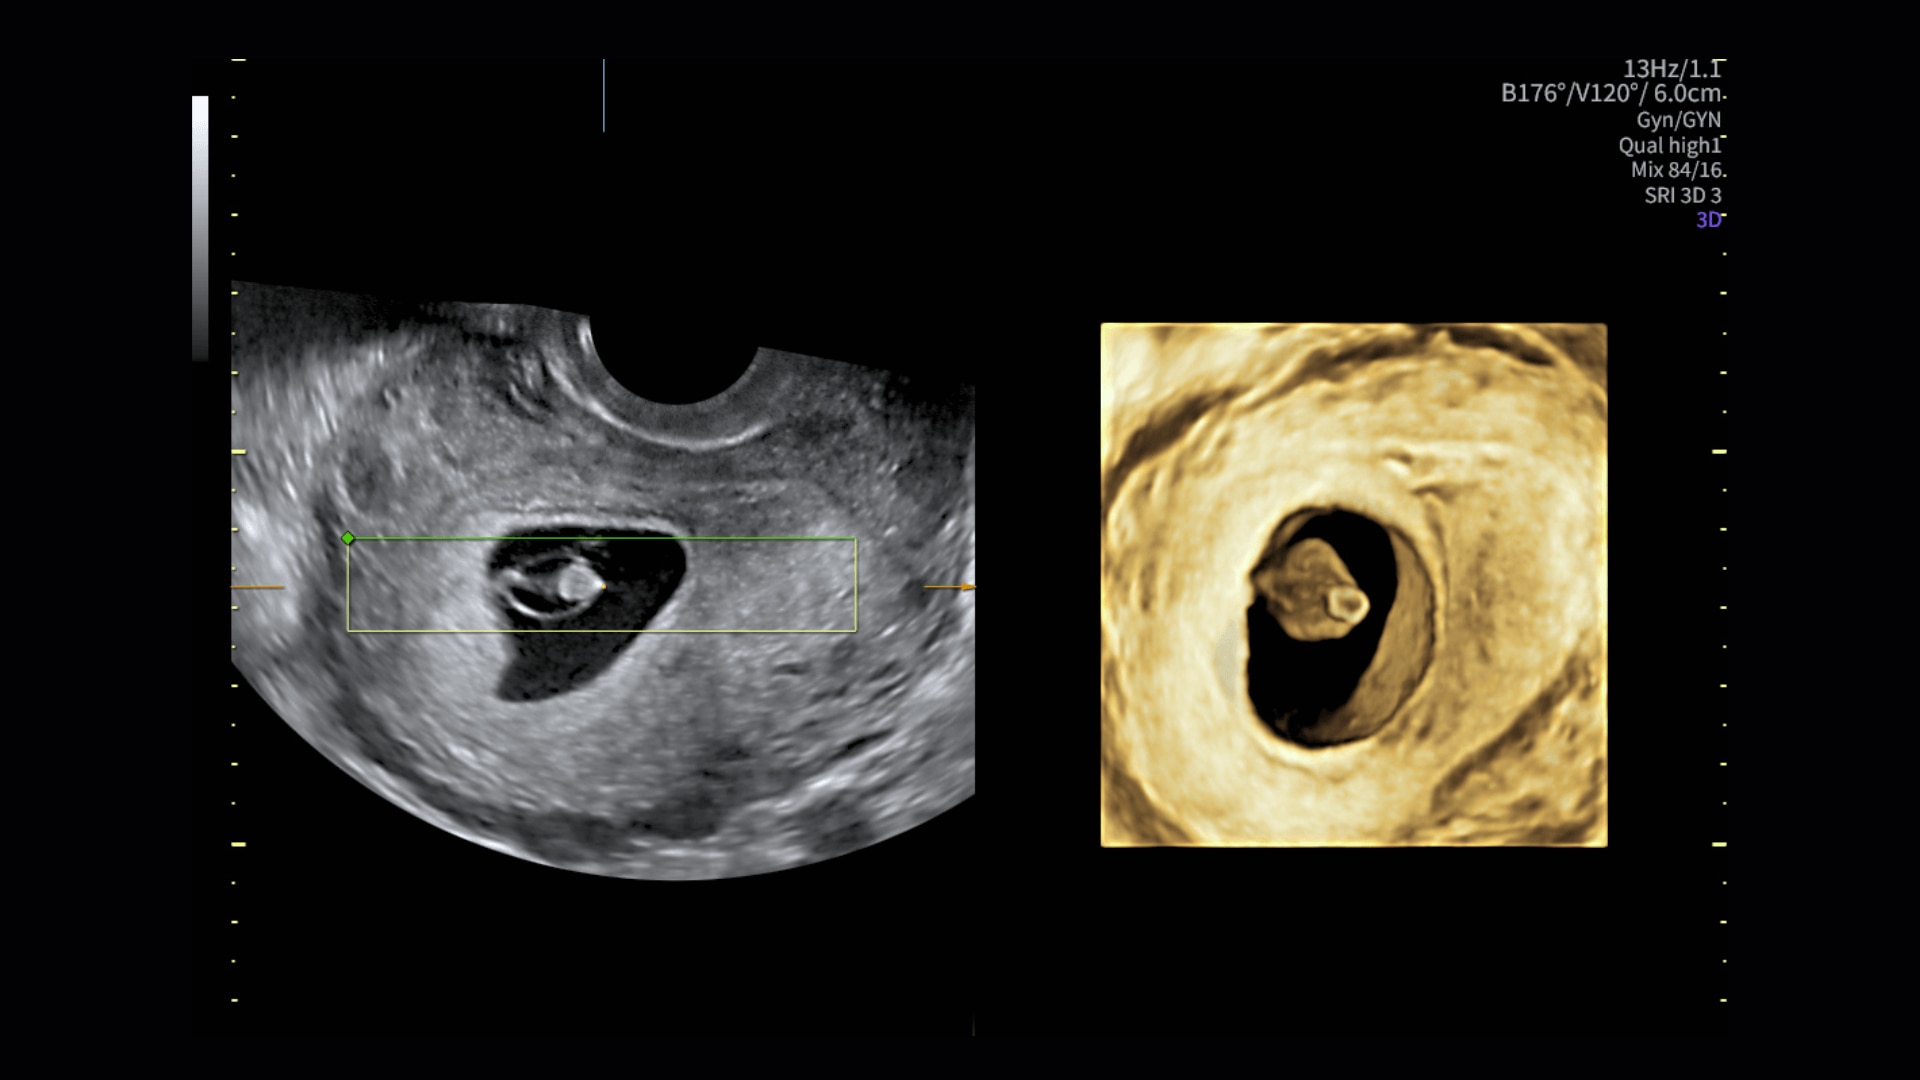

Image quality

Excellent images that are easy to acquire

Image quality is everything in ultrasound

The Voluson Performance 18 delivers high-resolution, detailed imaging with one-touch optimization for effortless scanning—helping you deliver quick, confident answers across a wide range of patient.